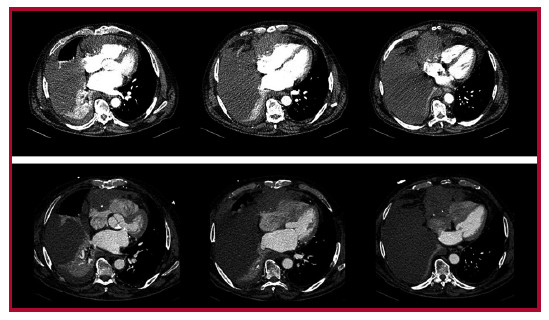

El electrocardiograma (ECG) mostraba ritmo sinusal, a 89 lpm con ondas T negativas de V1-V4, ya presentes en estudios previos. En la analítica se objetivó función renal normal (urea 31 mg/dL, creatinina 0,77 mg/dL, tasa de filtración glomerular 86 ml/ min/1,73 m2) con todos los iones en rango, proteína C reactiva 25,98 mg/L, lactato deshidrogenasa 950 U/L, creatinina kinasa 55 U/L, NT-proBNP 950 pg./mL, troponina T ultrasensible 25 ng/L, hemoglobina 11,2 g/dL, 335000 plaquetas, 11430 leucocitos, dímero D 4860 ng/mL. Para completar el diagnóstico, se realizó una tomografía computarizada (TC) no sincronizada en la que se describía una lesión hipodensa localizada sobre las cavidades cardiacas derechas (Figura 1). Como primera posibilidad diagnóstica se planteó un hemopericardio por rotura cardíaca o dehiscencia del bypass, siendo probable también el diagnóstico de una neoplasia. Ante estos hallazgos, se solicitó valoración por Cardiología. En el ecocardiograma (ETT) se objetivó una masa sólida y heterogénea en el saco pericárdico anterior, con adherencias en las cavidades derechas y compresión del surco auriculoventricular derecho, que no captaba contraste ecocardiográfico (Figura 2). El cuadro no impresionaba una rotura cardíaca, no solo por los hallazgos ecocardiográficos, también porque no había presentado dolor torácico ni alteraciones sugestivas de isquemia aguda en el ECG, y se encontraba hemodinámicamente estable, lo que, a su vez, hacía poco probable la dehiscencia del bypass.

Dada la discordancia, se decidió realizar una TC sincronizada para una mejor caracterización de la lesión, que mostró una masa pre-cardíaca derecha de 8,5 × 10 cm, de aparente dependencia pericárdica y que mostraba realce tras la administración de contraste intravenoso (Figura 1). Estos hallazgos planteaban el diagnóstico diferencial con metástasis o una neoplasia pericárdica primaria.